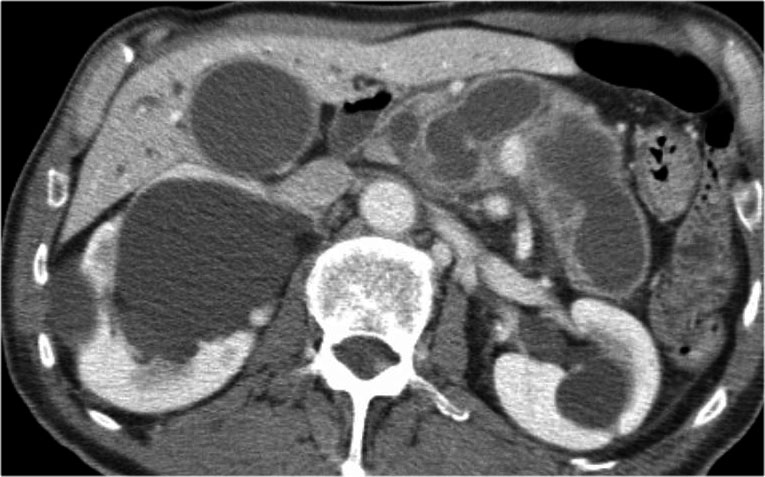

Hình ảnh CT của bệnh nhân nữ 30 tuổi có tiền sử viêm tụy do sỏi mật và đã cắt túi mật.

Bệnh nhân xuất hiện đau bụng trái đột ngột tăng nặng.

Siêu âm cho thấy tổn thương dạng nang tăng kích thước, được chẩn đoán là nang giả tụy (pseudocyst).

Tuy nhiên, CT cho thấy tổn thương dạng nang không có thùy hóa ở đuôi tụy với các vách ngăn bên trong có ngấm thuốc, không thông với ống tụy chính (hình).

Tiếp tục xem hình ảnh MRI…

Chuỗi xung T1W sau tiêm thuốc tương phản từ Gadolinium thể hiện rõ hơn các vách ngăn bên trong.

Phẫu thuật cắt đuôi tụy xác nhận u nang tuyến nhầy kích thước 14 cm có mô đệm buồng trứng (ovarian stroma).